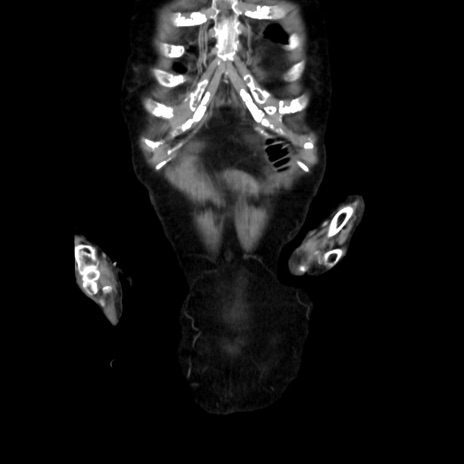

症例40(冠状断像)

冠状断像